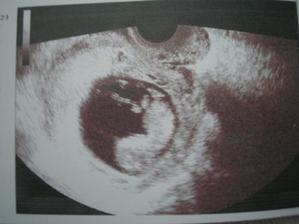

Tešíme sa z každého uzv a z každej kontroly, ktorá dopadne dobre, mamina musí ležať a drobček si zatiaľ krásne rastie. Prežili sme aj mesačný preventívny "all inclusive pobyt" v nemocnici.

V 32tt nám definitívne potvrdili, že čakáme chlapčeka... čo chlapčeka, riadneho chlapa, lebo odhad hmotnosti je 2400g.